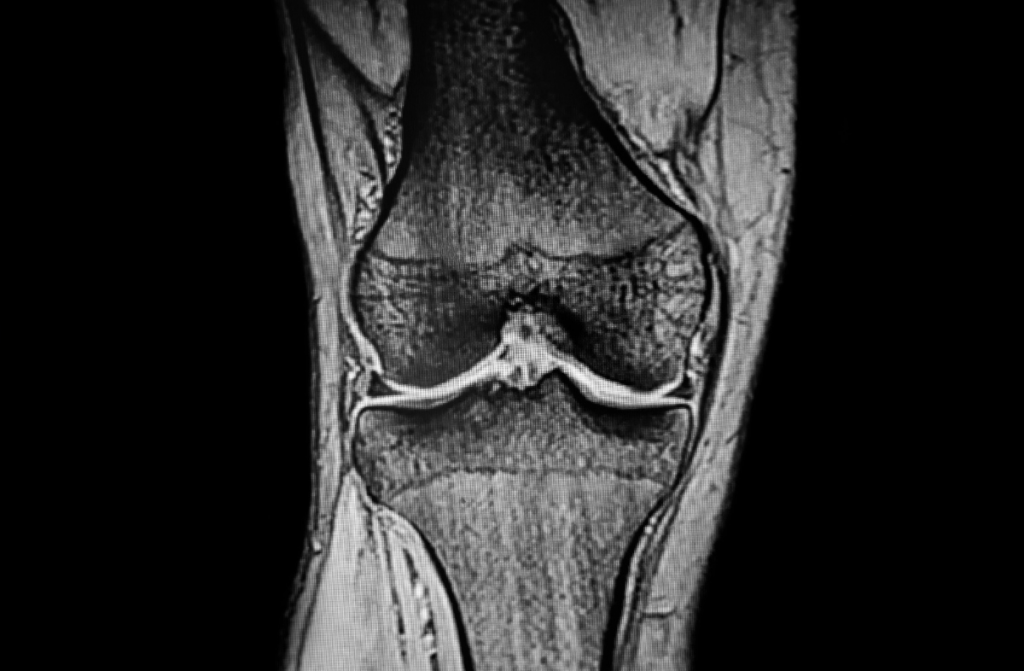

今回説明するMRI検査は、こうしたレントゲンを使う検査とは違い、磁気を使って関節の中や体の中を見ていく検査です。

一方でMRI検査は「形」だけでなく「内部の質」も評価できる、という点が大きな違いです。

さらにレントゲンやCTが「影をそのまま写し出す」のに対し、MRIは「信号をデジタル画像化」する検査になります。

MRIは体の中の水素分子の動きを見ています。

体に磁場(磁石の力)をかけてあげると水素が動くのですが、その動きの具合を評価して、そこから中がどうなっているかを調べる“質の検査”をしていくものになります。

MRI検査をすると、たとえばレントゲンでは見えない膝の半月板などの柔らかい組織が見えます。

骨の中での炎症もそのまま見えることがあり、炎症が起きている場所が白く映ってきたりします。

つまり、組織の「質」が評価できるということです。

再生医療においては、すごく深いところにある靱帯の状態が見えたり、骨の中の炎症が評価できたりします。

だからこそ、細かい状態を把握するためにMRIを使います。